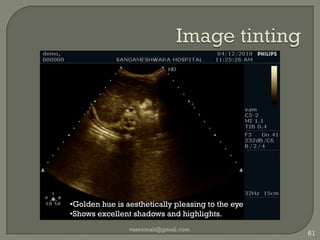

Image tintingvaseemali@gmail.com61Golden hue is aesthetically pleasing to the eye

Shows excellent shadows and highlights. Left right invertvaseemali@gmail.com62